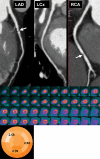

Positron emission tomography (PET) is increasingly being applied in the evaluation of myocardial perfusion. Cardiac PET can be performed with an increasing variety of cyclotron- and generator-produced radiotracers. Compared with single photon emission computed tomography, PET offers lower radiation exposure, fewer artifacts, improved spatial resolution, and, most important, improved diagnostic performance. With its capacity to quantify rest-peak stress left ventricular systolic function as well as coronary flow reserve, PET is superior to other methods for the detection of multivessel coronary artery disease and, potentially, for risk stratification. Coronary artery calcium scoring may be included for further risk stratification in patients with normal perfusion imaging findings. Furthermore, PET allows quantification of absolute myocardial perfusion, which also carries substantial prognostic value. Hybrid PET-computed tomography scanners allow functional evaluation of myocardial perfusion combined with anatomic characterization of the epicardial coronary arteries, thereby offering great potential for both diagnosis and management. Additional studies to further validate the prognostic value and cost effectiveness of PET are warranted.